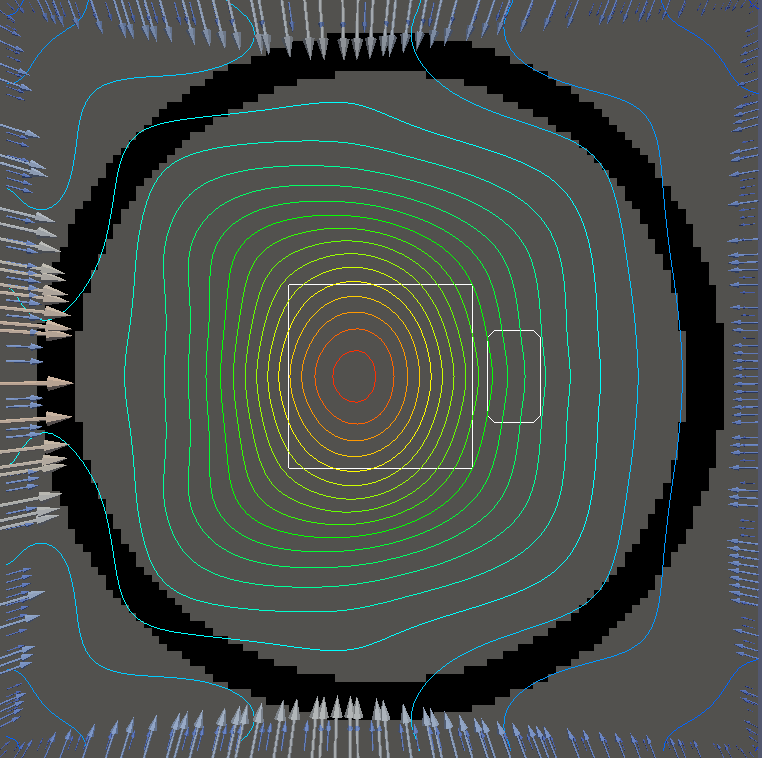

For testing, we use three tumor/risk region regions similar to those in [13]. Specifically, we define the regions in Table 3 and are shown in Figure 1; the void region is shown in black and the tumor and risk regions are traced in white. In the basic target case, seen in Figure 1(a), the tumor region is a box, as is the risk region. The second, intermediate target case, seen in Figure 1(b), involves an L-shaped tumor around a box-shaped risk region. Finally, the complex target case in Figure 1(c) involves a C-shaped tumor around a risk region.

Figure 2 shows the optimal boundary source term for both and The vectors shown on the boundary are the time-integrated values of normalized and then scaled by In Figures 2(a), 2(c), and 2(e) (corresponding to ), the isolines are spaced at intervals of the maximum of the desired dose (here, 5). In the intermediate and tracking cases, we see that relatively low dose levels are attained, primarily due to the high penalty to any dose deposited in the risk region. In Figures 2(b), 2(d), and 2(f)(corresponding to ), the isolines are spaced at intervals of of cells killed. Here a high proportion of the tumor cells are killed (in each case ) while in the Intermediate and Basic cases, the tumor has at least survival; in the Complex case, the risk region has survival.

The dose deposited in changes significantly when we alter the relative weights and . In Figure LABEL:fig:optlowrisk, we see the results for solving and where we set and (all other parameters are unchanged). In both the basic and intermediate cases, the dose delivered to the tumor is significantly higher while also remaining largely concentrated on the tumor. This is slightly less true in the complex case. In the figures for there is no general change in the pattern of cell death, however the risk region in the first two cases has cell survival whereas the complex case has approximately cell survival. However, this lack of change in pattern can partially be attributed to the tumor cells being more susceptible to the radiation dose.